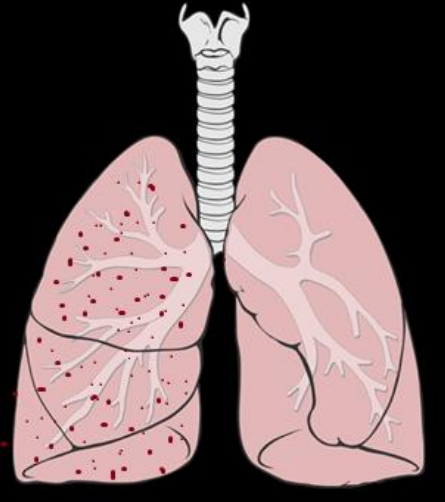

24

Q

¿Qué patrón tiene la lx?

A

Miliar

How well did you know this?